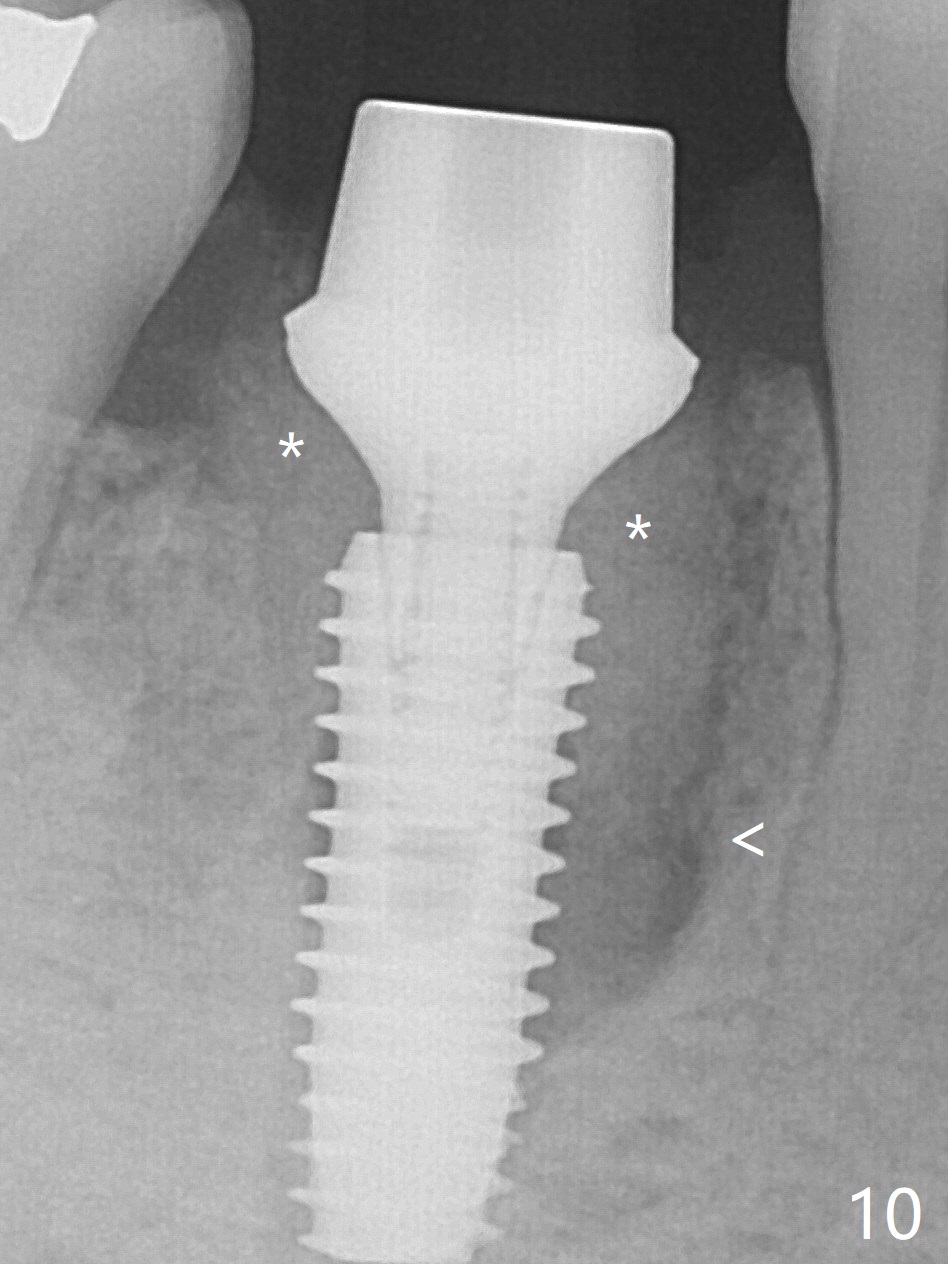

Preop oral Amoxicillin seems to be associated with reduction in the buccal and lingual (Fig.3 arrow) fistulae at #30, but there is mesiobuccal swelling (Fig.1 *) with 7 mm pocket (Fig.2). Osteotomy is initiated in the middle of the septum (Fig.3-5 S). As the osteotomy increases, it shifts mesially (Fig.6 arrow). Guided surgery is able to reduce shifting. A 5x13 mm implant is not seated completely (Fig.7) apparently due to osteotomy shifting. After removal of the bone from the osteotomy distally, the implant remains unseated with lower torque value (Fig.8). Following reuse of the 4.3 mm drill deeper by 1-2 mm, the implant is seated to a satisfactory depth (Fig.9 with increase in torque to 50 Ncm) with placement of Vera Graft (*) and a 7.5x4(3) mm abutment. After a second round of allograft placement (Fig.10 *), the implant is found to be 4 mm from the IAC. At the later stage of osteotomy, the coronal end of the septum is destroyed with loss of osteotomy depth landmark. It is apparent that the soft tissue landmark may be more reliable. The implant threads appear to be covered by the bone graft 3.5 months postop (Fig.11). The abutment is changed to 6.5x5(3) mm one before impression with minor margin prep. The bone density seems to increase 5 months postop, i.e., immediately post cementation (Fig.12) and 10 months postop (5 months post cementation (after retightening abutment), Fig.13 (*)). Periimplantitis develops mesiobuccally, consistent with bone loss 1 year 7 months post cementation (Fig.14 *); the implant seems to have been buccally placed. Bone graft is necessary with PRF or GEM21S if the vein is small and 6-month membrane with a hole around a 7.5x4(4) cemented abutment for easy wound closure. Take 5x5 CM CBCT to determine which wall has defect, buccal or lingual. Check mesial contact. If so, remove the crown, reseat the abutment (possible incomplete seating) and re-impress after bone graft.